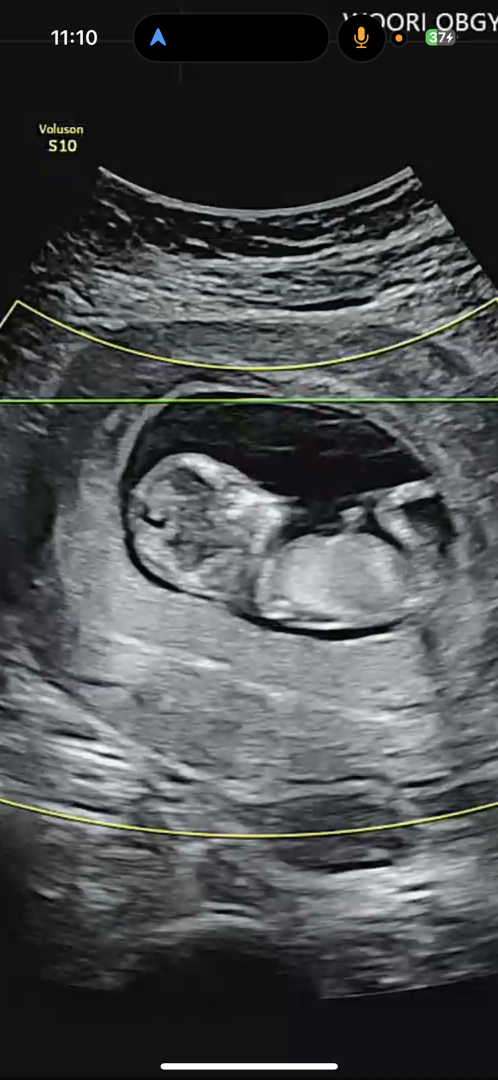

12주 성별 각도법 부탁드립니다!

분만병원 초음파가 선명하지 않은 것으로 유명해서ㅠㅠ 제일 잘 나온 것으로 올려봅니다ㅠㅠ 사진은 12주1일차입니다 각도법 잘 아시는 분들 답변 남겨주시면 대단히 감사드리겠습니다! 모두 좋은 하루 되세요!